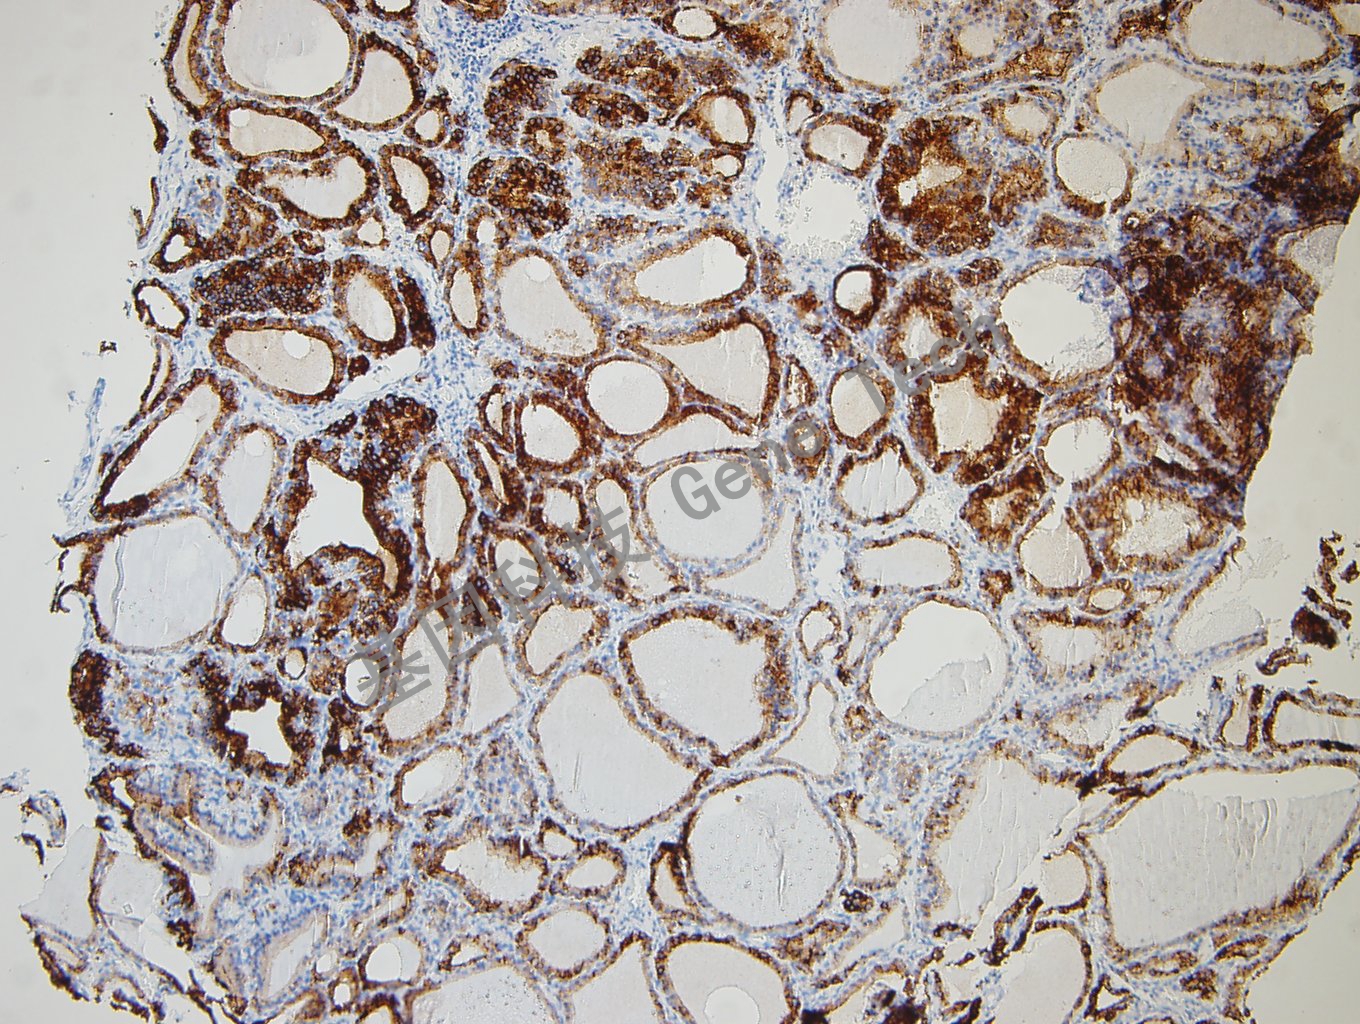

TPO(Thyroid peroxidase, 甲状腺过氧化物酶)由甲状腺滤泡细胞合成,位于甲状腺上皮细胞的顶端游离面上,直接参与甲状腺细胞中碘的氧化,酪氨酸的碘化及碘化酪氨酸的偶联等,它是甲状腺激素合成过程中的关键酶。在正常、增生性及绝大多数良性肿瘤性甲状腺组织中高度表达,在甲状腺恶性肿瘤中TPO表达明显减少。该抗体主要用于甲状腺组织良、恶性肿瘤的鉴别诊断。

甲状腺癌石蜡切片,用TPO(GT2440)染色,细胞浆阳性,DAB显色。

甲状腺瘤石蜡切片,用TPO(GT2440)染色,细胞浆阳性,DAB显色。